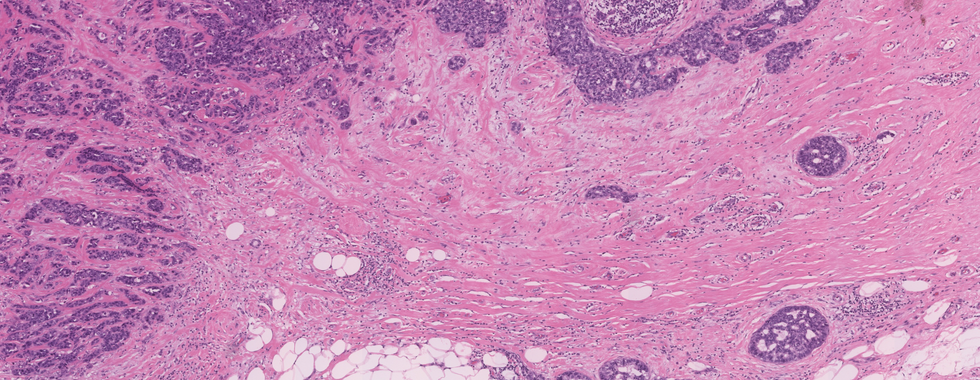

Diagnosis: Invasive ductal carcinoma (NOS), grade 3 with a focus of DCIS

Infiltrating duct carcinoma NOS

● The most common subtype of invasive breast carcinoma, comprising 70% to 75%.

● The growth pattern of this tumor is heterogenous that can be solid, trabecular, in cords, in tubules, or as single cells

● The tumor cells show moderate to marked pleomorphism.

● Abundant and eosinophilic cytoplasm. Nuclei may be highly pleomorphic, or regular with prominent nucleoli and glandular pattern may be extensive or absent.

● A highly cellular desmoplastic stromal fibroblastic proliferation, a scanty connective tissue element, or marked hyalinization may be seen.

● Focal necrosis may be present (seen in approximately 60% of cases)

● The prominent lymphoplasmacytic response was seen in 15% to 20% of cases.

● In the high-grade tumor, angiolymphatic or perineural invasion often seen